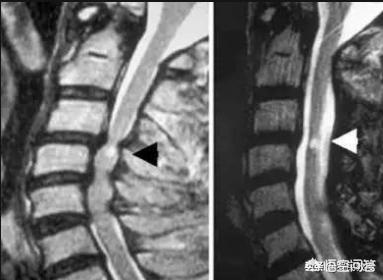

2.脊髄頚椎症:頚椎後縁の過形成、椎間板の後方ヘルニア、靭帯肥大、後縦靭帯の石灰化などが主な原因。手足の脱力や物を持つときのふらつきなどの症状を引き起こすこともある。

これらの状態は、頚椎症によって神経根や脊髄が強く圧迫されていることを示しており、このような実質的な圧迫に対しては、薬物療法や理学療法だけに頼っていては効果が少ないことが多い。また、脊髄の圧迫、すなわち脊髄性頚椎症に対しては、牽引やマッサージが症状を悪化させ、半身不随につながることさえあります。